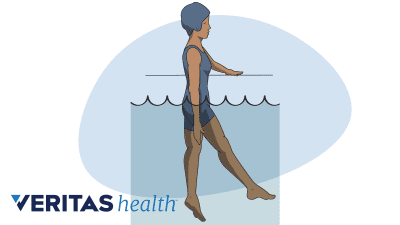

Water therapy or aquatic therapy is an excellent choice for anyone who has too much back pain and/or joint pain for land-based physical therapy.